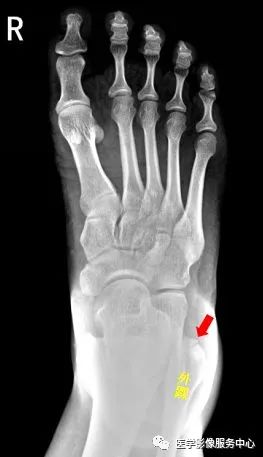

右侧外踝骨皮质连续中断,可见透亮骨折线影,可见软组织稍肿胀影,右踝关节骨折。

Warmreminder:踝关节扭伤,许多大夫只做踝关节正侧位。有时踝关节正侧位不能看出有明显异常,而有局部软组织肿胀,活动受限时,根据我的经验,踝关节扭伤有时只做正侧位是有局限性的;小妙招:足正位也是必不可少的。

此患者就是踝关节扭伤,踝关节正侧位未见异常,加拍足正位时发现外踝骨折。

右足第5跖骨基底部见骨折线,断处稍分离移位,右足第5跖骨基底部骨折。

Warmreminder: 儿童时期足第5跖骨处有骨骺存在,骨骺线易与骨折线混淆。

小妙招给你:骨骺线的长轴一般是与第5跖骨长轴平行,而第5跖骨多是横行骨折,换言之骨折线与第五跖骨长轴垂直。